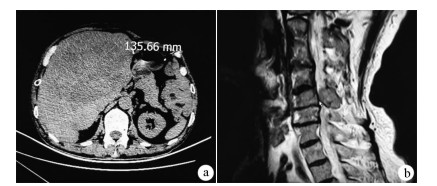

Hepatocellular carcinoma with intraspinal metastasis initially manifesting as cervical cord compression: A case report

Fu WEI, Jian WANG, Caini HE, Yunyu ZHAO, Fengtao LI, Fanpu JI

2021, 37(1): 156-157. DOI: 10.3969/j.issn.1001-5256.2021.01.031

Abstract(1100) HTML (362) PDF (2235KB)(50)

Abstract: